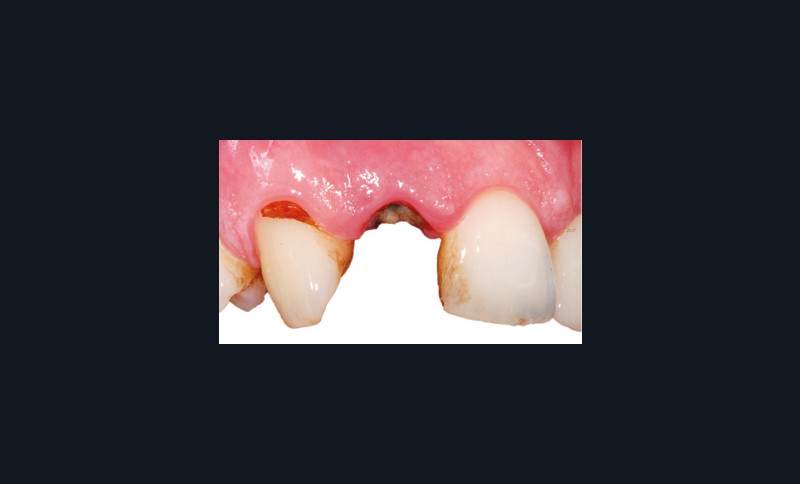

Nous allons décrire, étape par étape, les différents temps cliniques permettant l’élaboration d’un guide chirurgical et la place de la CFAO de la planification à la réalisation du temps chirurgical au travers d’un cas clinique (fig. 1).

L’édentement concerné et l’arcade antagoniste sont enregistrés à l’aide d’une empreinte optique intra-orale (fig. 2) ou d’une empreinte physico-chimique. Cette dernière devra être numérisée avec un scanner de table, nous permettant d’obtenir un fichier STL. L’info-prothésiste modélise alors un wax-up numérique, en veillant à l’intégration de la future restauration prothétique.